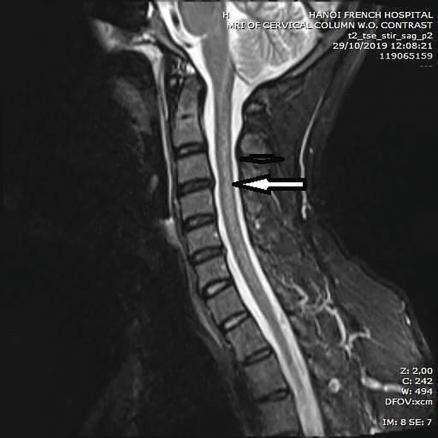

Cet homme de 36 ans, sans antécédent particulier, consultait pour des sensations de peau cartonnée aux pieds et aux mains évoluant depuis trois semaines. Il rapportait la consommation journalière depuis un mois de 40 ballons de protoxyde d’azote (NO). L’examen notait la présence d’un signe de Lhermitte déclenché par l’antéflexion céphalique, des réflexes ostéotendineux vifs et symétriques, une apallesthésie des membres inférieurs et une sensibilité superficielle préservée, sans déficit moteur associé. Le bilan biologique montrait un déficit en vitamine B12 à 179 pg/mL (211-911) et une homocystéinémie supérieure à 50 µmoles/L (5-15). L’IRM cervicale montrait une lésion médullaire postérieure étendue, localisée aux cordons postérieurs (fig. 1 et 2 ).